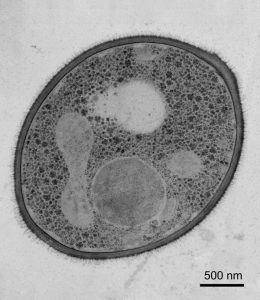

真菌病原体如Cryptococcus neoformans.,白色念珠菌和C. lusitaniae.的近亲C. Auris.他们通常会重新配置染色体,以帮助自己适应压力大的环境。很显然,C. Auris.也是如此。在测试了来自四个地理“震中”的26个临床分离株后,Lorenz和他的团队发现,即使是最密切相关的菌株也有不同的染色体数目,东亚菌株有5到7条染色体,而南亚菌株有6到7条染色体,尽管它们共享相对统一的DNA序列。它们差异的关键,至少部分在于DNA的稳定性——或者更确切地说,是它的不稳定性。根据洛伦茨的说法,在1到4条染色体之间有一种被称为核糖体DNA (rDNA)的基因的重复拷贝,这种基因在其他酵母中已经被证明是易挥发的。事实上,这些“rDNA重复”通常与总体染色体重排有关——导致了遗传多样性的增加,基因表达的改变和对挑战性环境的潜在适应。

在所有情况下,染色体出现,消失或改变尺寸,频率和改变类型根据所用的应变和条件而不同。然而,很少的修改 - 主要是东亚和南美菌株的修改 - 实际上导致增长改善。但是值得注意的是,他们也没有妨碍可行性或增长。

这在南非菌株中尤其引人注目,在高温胁迫下,该菌株在将其基因组从7个染色体合并到3个染色体后继续增长。研究人员称,酵母可能是通过端到端连接染色体或将其染色体分离并与其他染色体融合来实现这一目标的。这种剧烈的变化可以提供适应的机会,而不是浪费细胞的生存能力C. Auris.研究人员补充道。

尽管拥有相对一致的DNA序列,但即使是关系最密切的菌株也有不同的染色体数目。